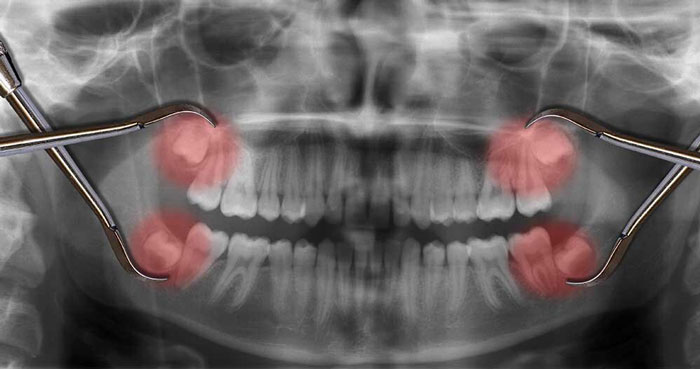

دندانهای عقل با قرارگیری غیرعادی و اغلب بدون رویش دندانهای نهفته نامیده میشوند. این دندان ها نه تنها دردناک هستند، بلکه خطر جدی برای سلامت دهان و دندان شما نیز به همراه دارند.

دندان های عقلی که در زیر خط لثه قرار گرفته اند، خوش خیم نیستند. اکثر دندان های عقل به دلیل خوابیدن به پهلو، قرار گرفتن در یک زاویه یا مسدود شدن به دلیل محدودیت فضا، بیرون نمی آیند. در برخی موارد، دندان عقل فقط تا حدی از طریق لثه بیرون می زند.

عفونت دندان عقل نهفته، حتی می تواند به سایر قسمت های بدن سرایت کند. علاوه بر این، آبسه میتواند ایجاد شود که سپس به ریشه دندانهای اطراف آسیب میرسانند و تکیهگاه استخوان را فرسایش میدهند.